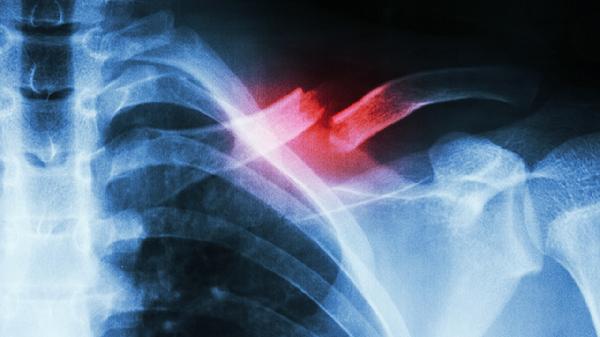

1、外伤:

胸部直接撞击或挤压可能导致肋软骨损伤,引发无菌性炎症反应。常见于交通事故、运动碰撞等场景。急性期需制动休息,慢性期可配合热敷促进血液循环。